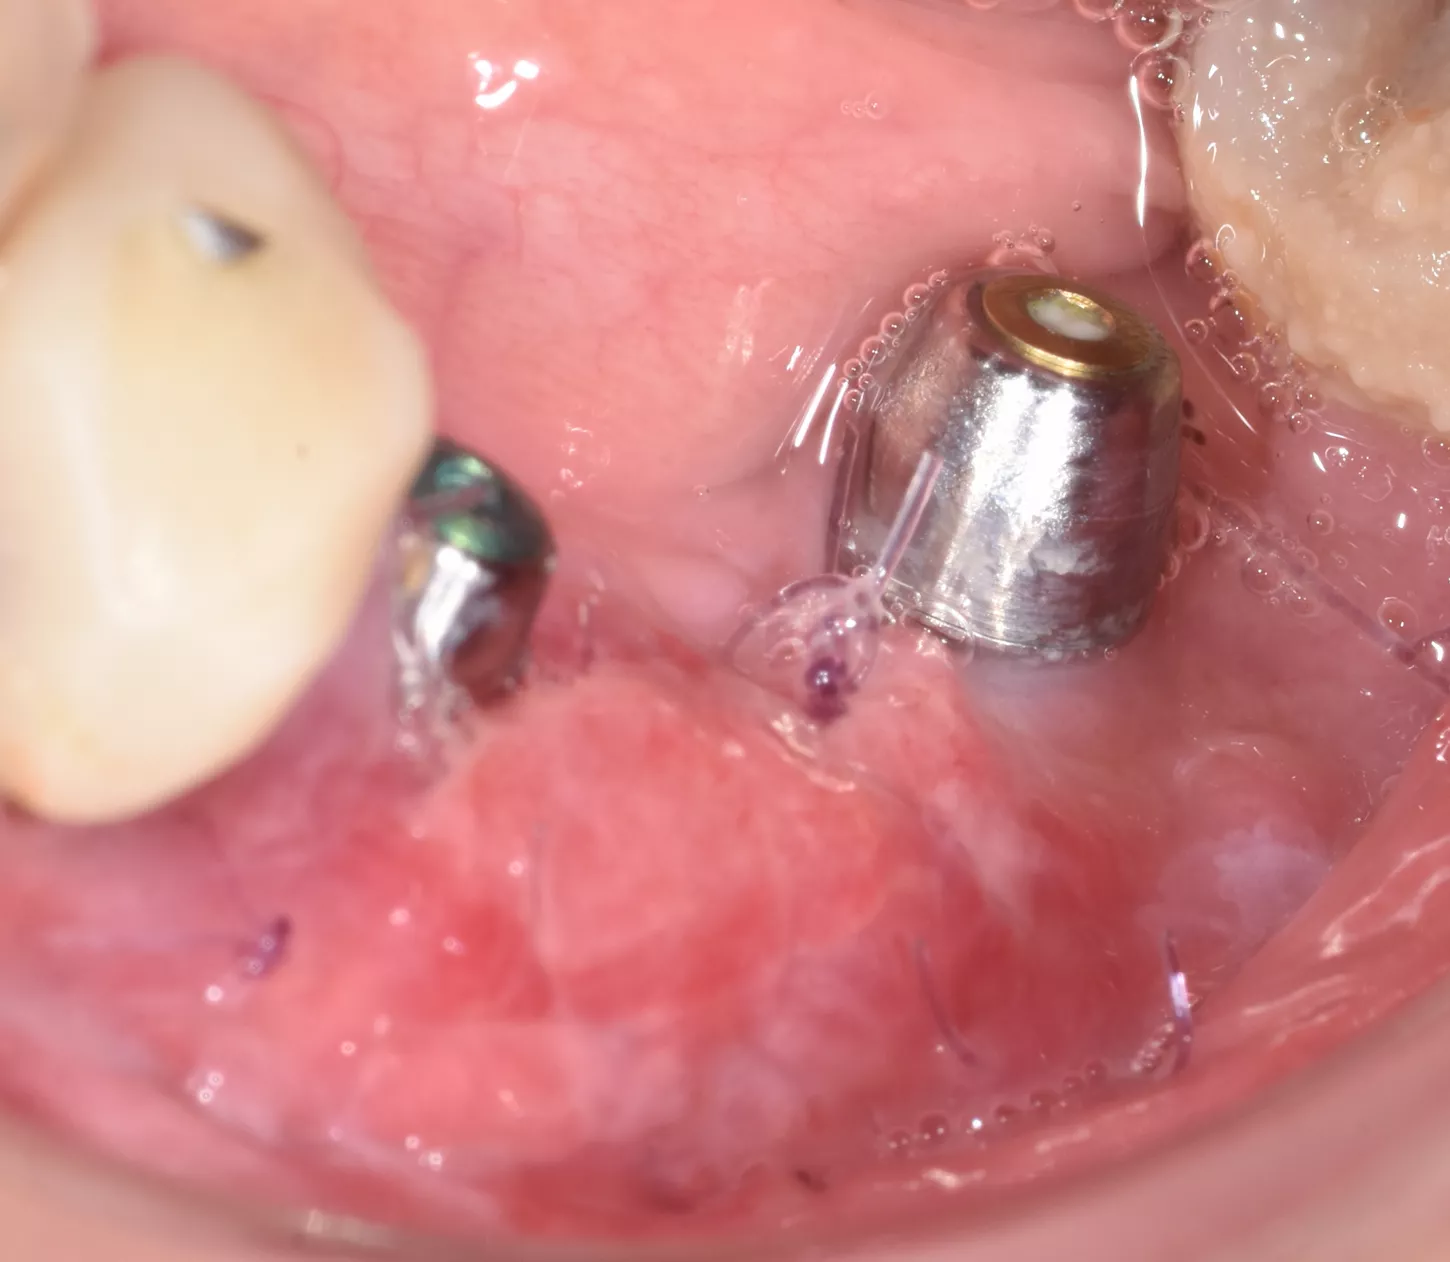

7. 3 months later: to increase the amount of keratinised tissue, connective epithelial graft with positioning of 2 multi-unit abutments with on the implants was done. ISQ 75.